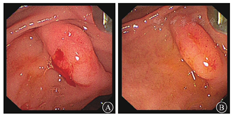

入院后予输注悬浮红细胞、抑酸护胃、补铁等治疗,患者未再出现呕血、黑便,大便隐血试验阴性。胃镜检查示十二指肠乳头处活动性渗血(图2)。腹部增强MRI检查示:①轻度肝硬化,轻度脂肪肝,动脉期肝脏异常强化灶,考虑异常灌注,左肝小囊肿。②脾大,脾部分梗死考虑,脾静脉显示不清,胃前方侧支形成;脾静脉与肠系膜上静脉汇合处血栓形成可能;脾动脉瘤。③考虑慢性胰腺炎。④胆囊底壁稍厚,胆囊腺肌症可能;右肾小囊肿。遂在介入科行脾动脉瘤栓塞术。术中见脾动脉局部囊袋样凸起,直径约8 mm,未见明显造影剂外溢,使用可控弹簧钢圈和栓塞胶进行栓塞(图3)。术后造影检查显示脾动脉主干及其远端分支显影良好,脾动脉瘤未见确切显示。患者术后多次复查血常规,血红蛋白水平维持在90 g/L以上。后复查胃镜示十二指肠乳头仍有活动性出血。遂行超声胃镜检查,内镜下见胃底、胃体上段多条曲张静脉,部分成团、成球样改变(图4A);十二指肠乳头结构无特殊,其开口可见墨绿色胆汁溢出;超声胃镜检查见胰腺实质回声不均匀,散在较密集点片状高回声区,呈云朵样;胰管显示,管壁回声增粗、增强;胆总管显示,胰头段胆管壁增厚;胰腺尾部见一3.0 cm×1.9 cm无回声区(图4B),部分囊壁呈片状增厚;脾脏显示增厚。诊断:慢性胰腺炎;胰尾部囊性病变,性质待定;重度胃底静脉曲张。对症支持治疗后患者未再解黑便,复查血红蛋白水平稳定,患者拒绝进一步检查,要求出院随访。

2018年2月11日,患者因"再发黑便1周"再次入住浙江大学医学院附属邵逸夫医院消化内科。查血常规示红细胞计数为1.84×1012/L,血红蛋白为34 g/L,平均红细胞体积为65.9 fL,平均血红蛋白水平为279 g/L。胃镜检查示十二指肠乳头搏动性出血,中重度胃底静脉曲张。胃镜下乳头冲洗后间断可见黄绿色胆汁流出,考虑胰管来源出血可能性大。急诊腹部增强CT检查示脾动脉瘤复发,行急诊脾动脉造影术和脾动脉栓塞术,脾动脉局部可见造影剂外溢,考虑活动性出血(图5);超选栓塞后造影见破裂口处闭塞,远端脾动脉通过侧支部分代偿,术中证实为脾动脉瘤破裂入胰管引起消化道出血。病情稳定后出院,随访5个月患者未再发呕血、黑便,复查血红蛋白水平在正常参考值范围内,大便隐血阴性。